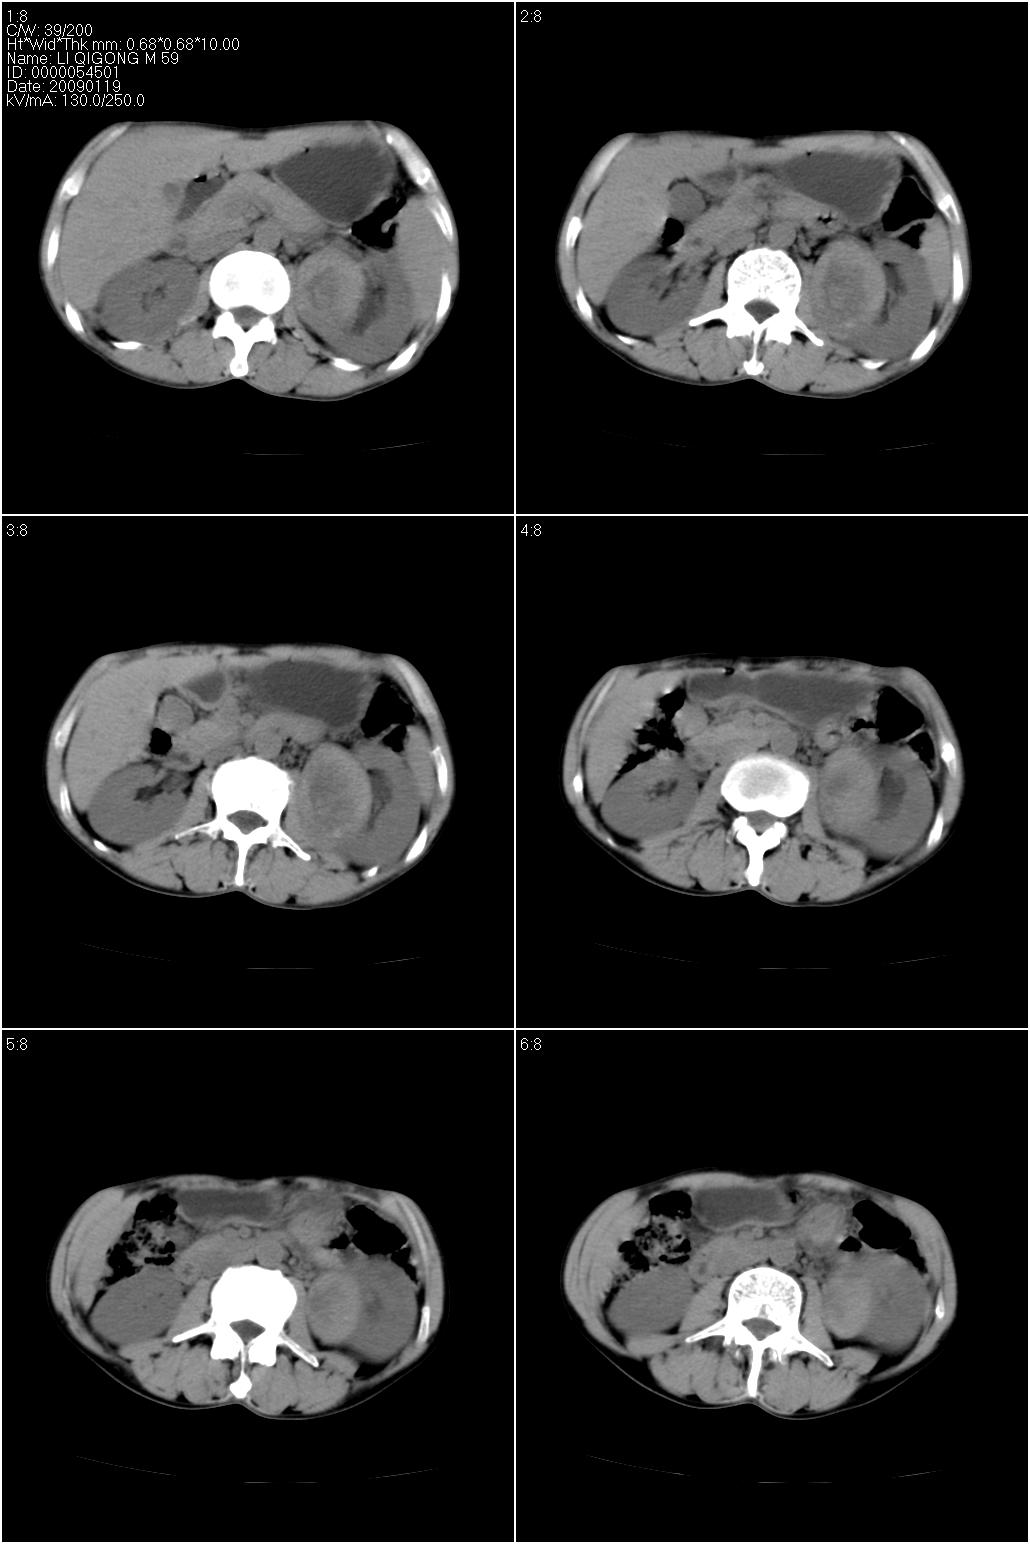

男性,59岁。体检发现左肾占位。自诉无尿血、尿痛。

无痛无血尿,左肾实质占位,有明显强化,中心坏死不规则,应该肾癌无疑。

应该考虑左肾癌并肾盂积水

诊断依据:

1、中老年男性.

2、左肾占位,呈不均匀性强化,中央有无强化的坏死区。

3、左肾门旁有侧枝开放,提示左肾静脉癌栓形成可能。

4、患者自诉无血尿,但不一定镜下无血尿。